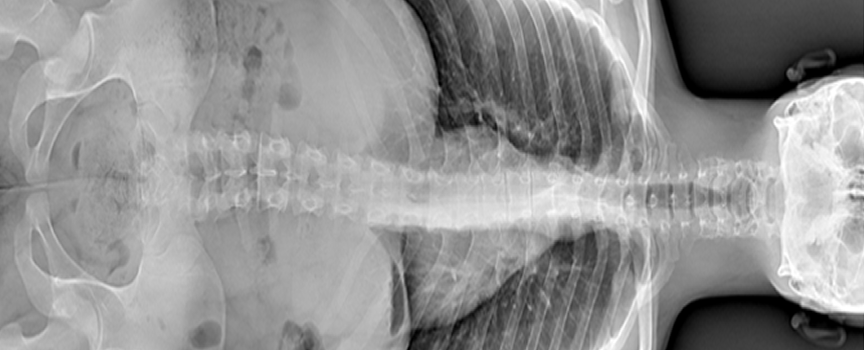

System kostno-płucny

Łączenie (stitching)

Automatyczny i zsynchronizowany ruch lampy rentgenowskiej oraz detektora umożliwia precyzyjną rekonstrukcję długich odcinków szkieletu. W efekcie otrzymujesz jeden idealny, połączony obraz z minimalną ilością artefaktów ruchowych.